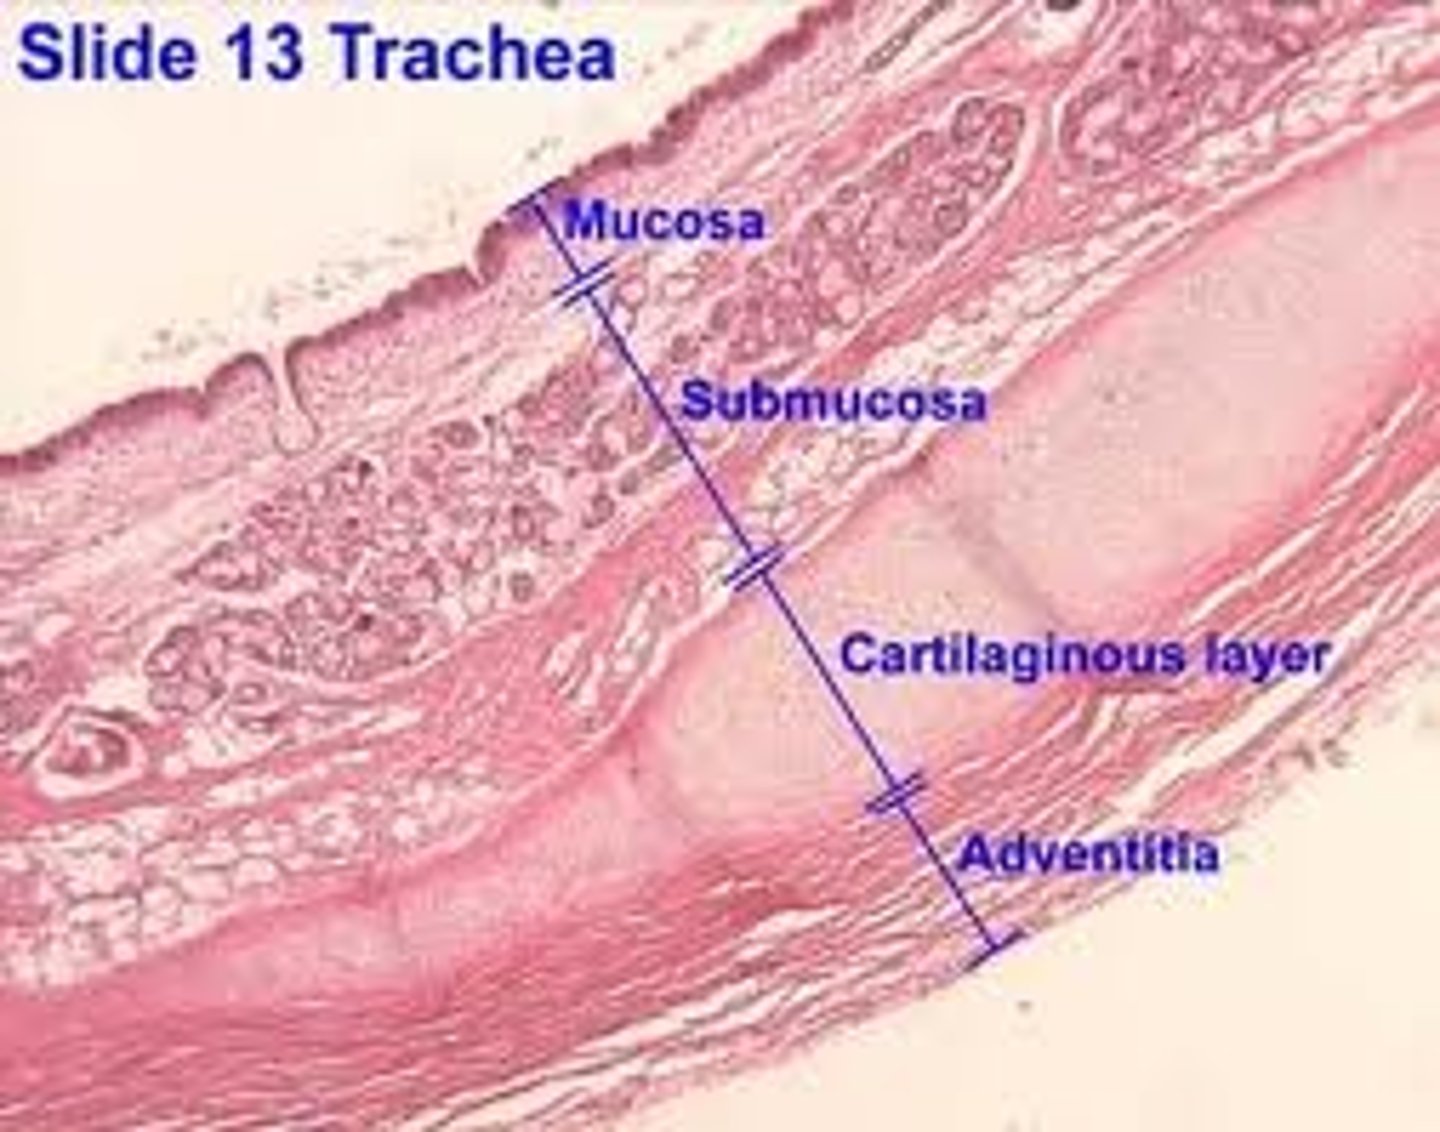

What layers make up the trachea?

Mucosa, submucosa, cartilaginous layer, adventitia.

What does the submucosa contain?

Dense irregular CT and glandular elements.

What type of cartilage supports the trachea?

Hyaline cartilage (16-20 C shaped rings)

What is the adventitia?

Connective tissue layer deep to cartilage

What does the adventitia contain?

Large blood vessels and lymphatic tissue.